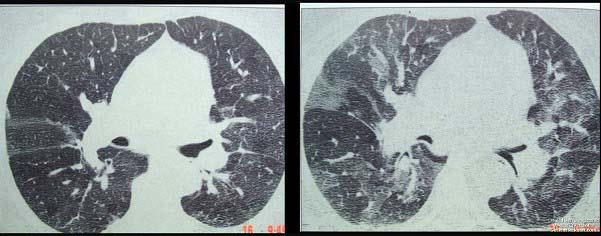

问题 患者轻微咳嗽,实验室检查嗜酸粒细胞升高,影像学检查如图,两次检查时间相距8小时,最可能的诊断为 ( )

选项 A.双下肺肺炎 B.军团菌肺炎 C.金黄色葡萄球菌肺炎 D.支原体肺炎 E.过敏性肺炎

答案 E